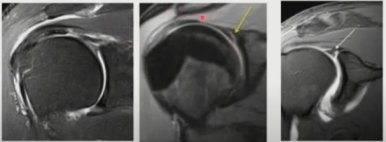

▶ SLAP lesion 4type

- 제1형 : 관절와순은 관절와에 부착되어 있으나 마모 및 변성이 있는경우(이두장건 부착부는 분리되지 않은 상태)

- 제2형(가장 흔한 유형) : 관절와순 및 이두장건의 박리가 있는경우(이두장건 부착부위가 파열되어 일부 분리)

- 제3형 : 양동이 손잡이 파열로서, 상부관절와순이 파열되어 관절안으로 전위되었으나 이두장건 부착부위는 손상이 없는경우

- 제4형 : 상부관절와순의 파열이 이두장건까지 연장되어 있으며 관절안으로 전위되어있는경우로서 드문 유형입니다.

MRI

- SLAP은 MRI상에서 type별로 아래와같이 관찰될 수 있습니다.